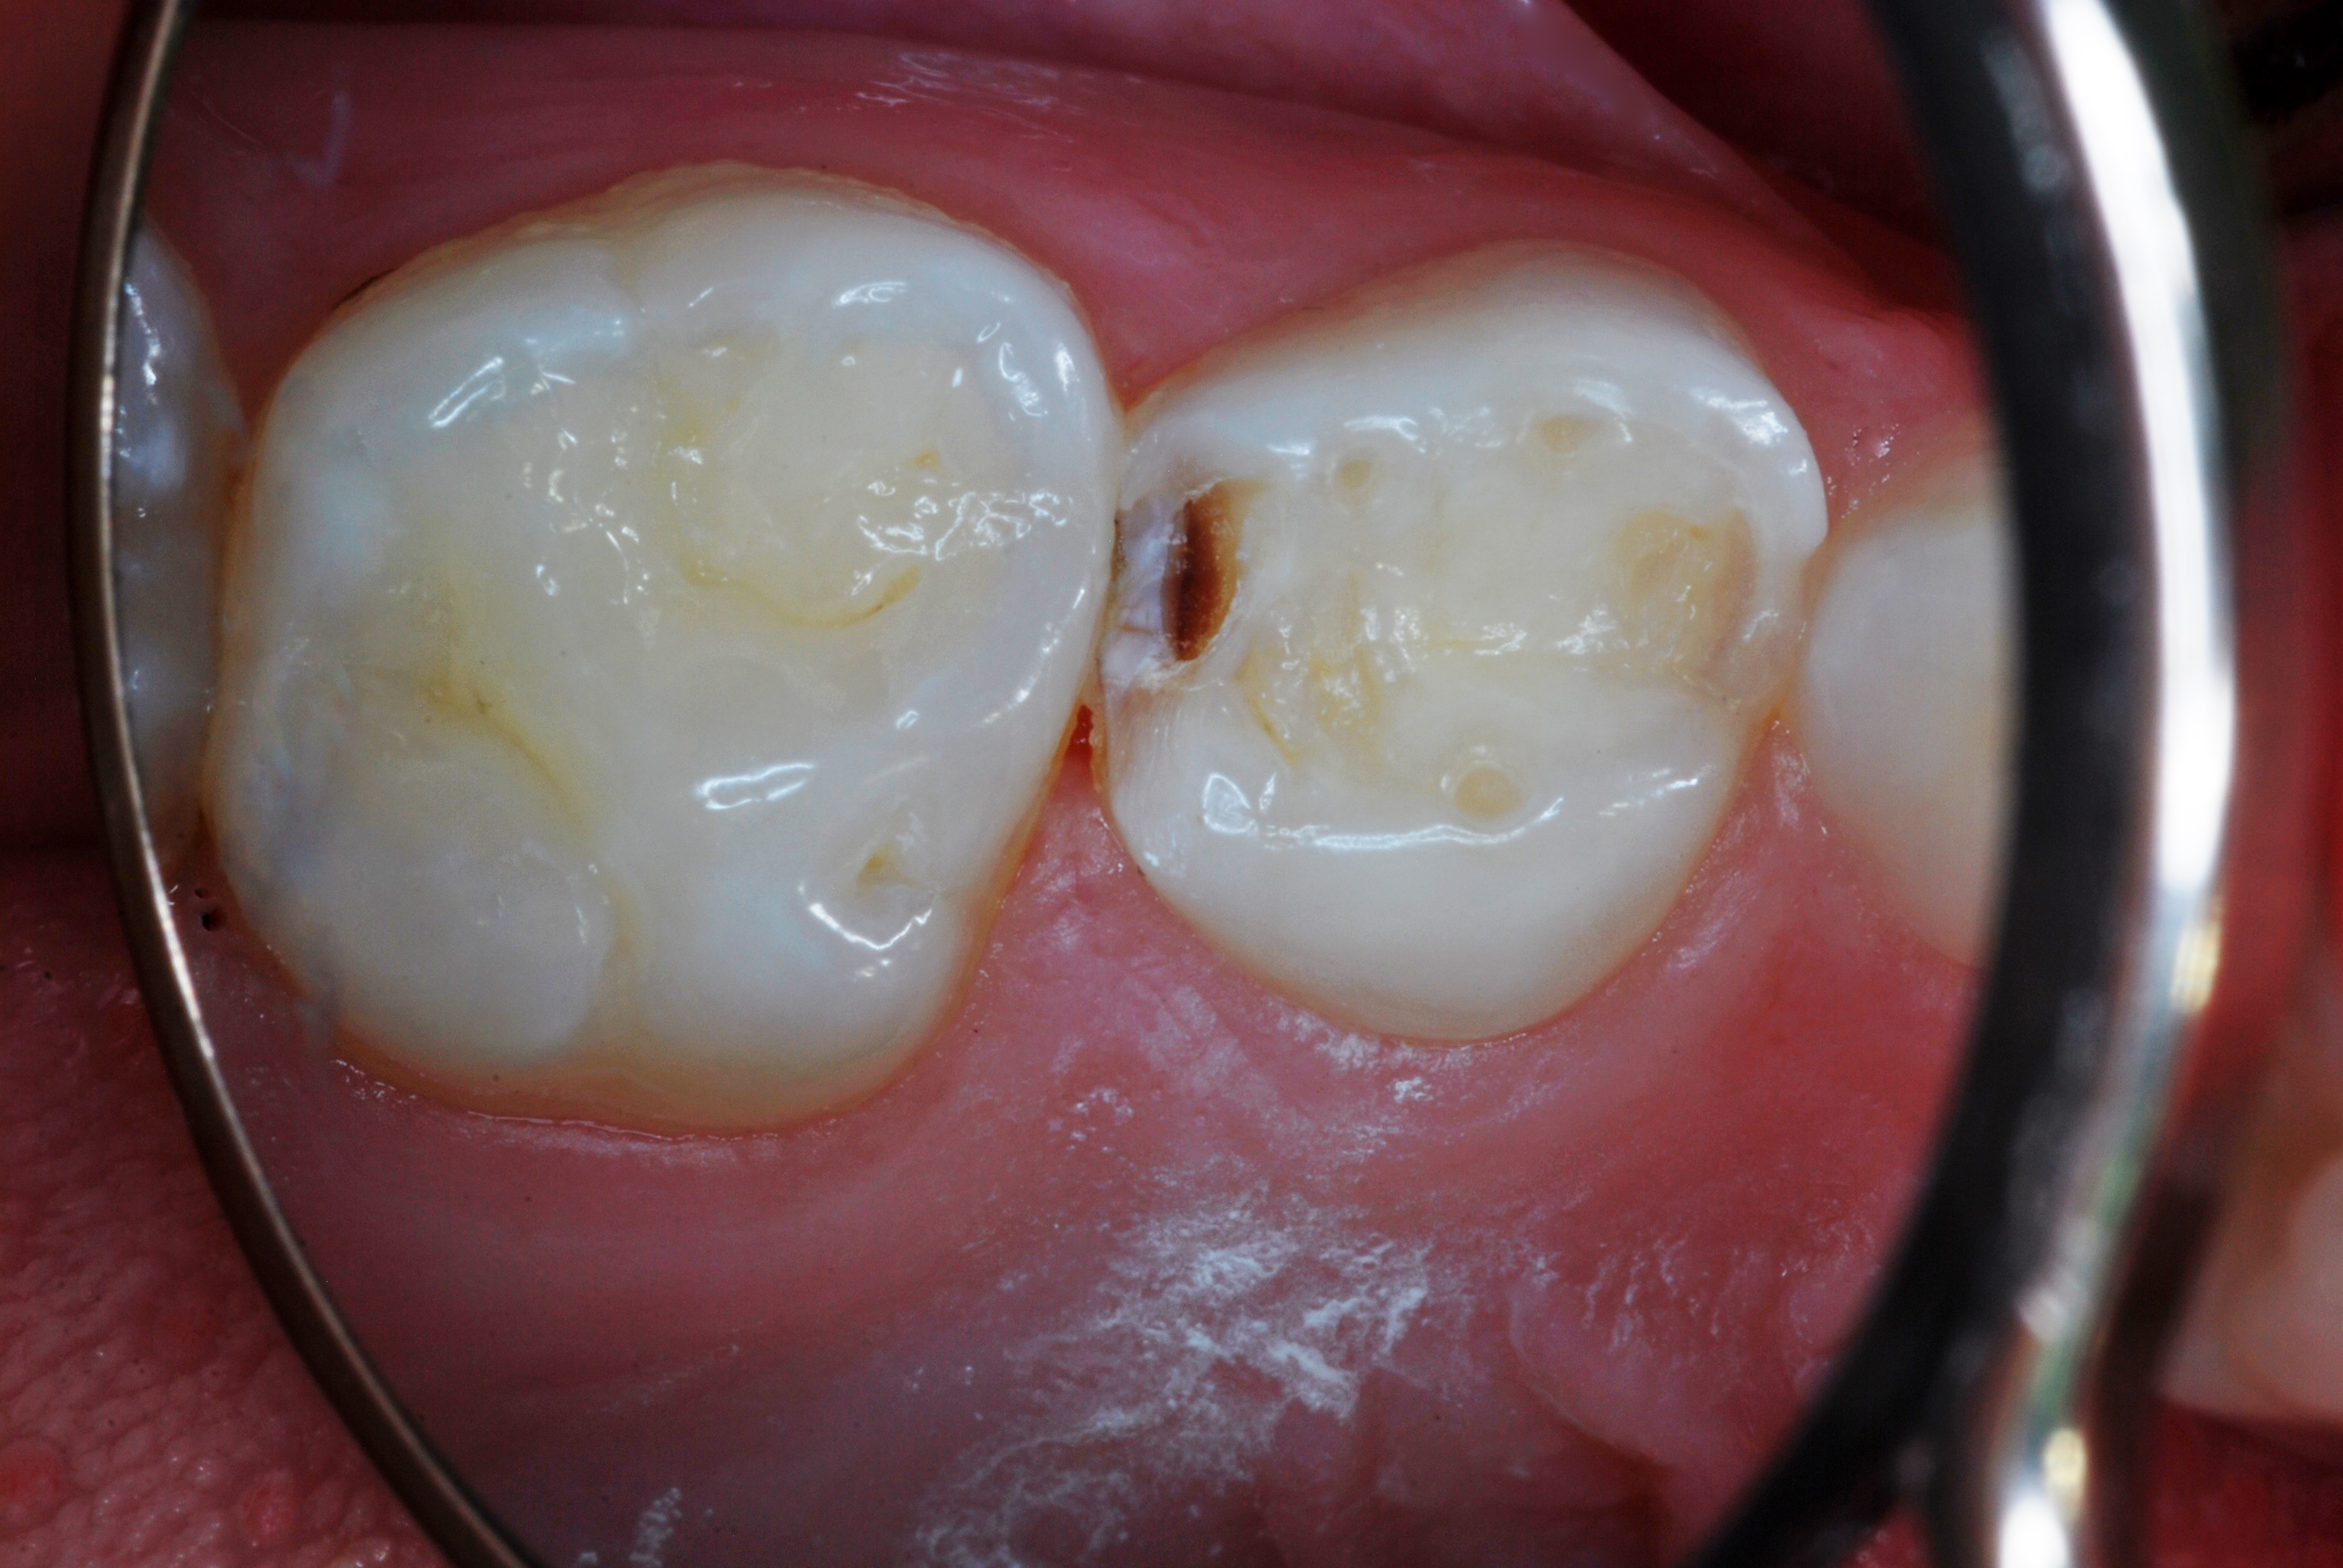

(23.) Teenage patient who had SDF applications every four months for 16 months. Flossing compliance was poor, and several teeth will require restorative care.

Figure 23